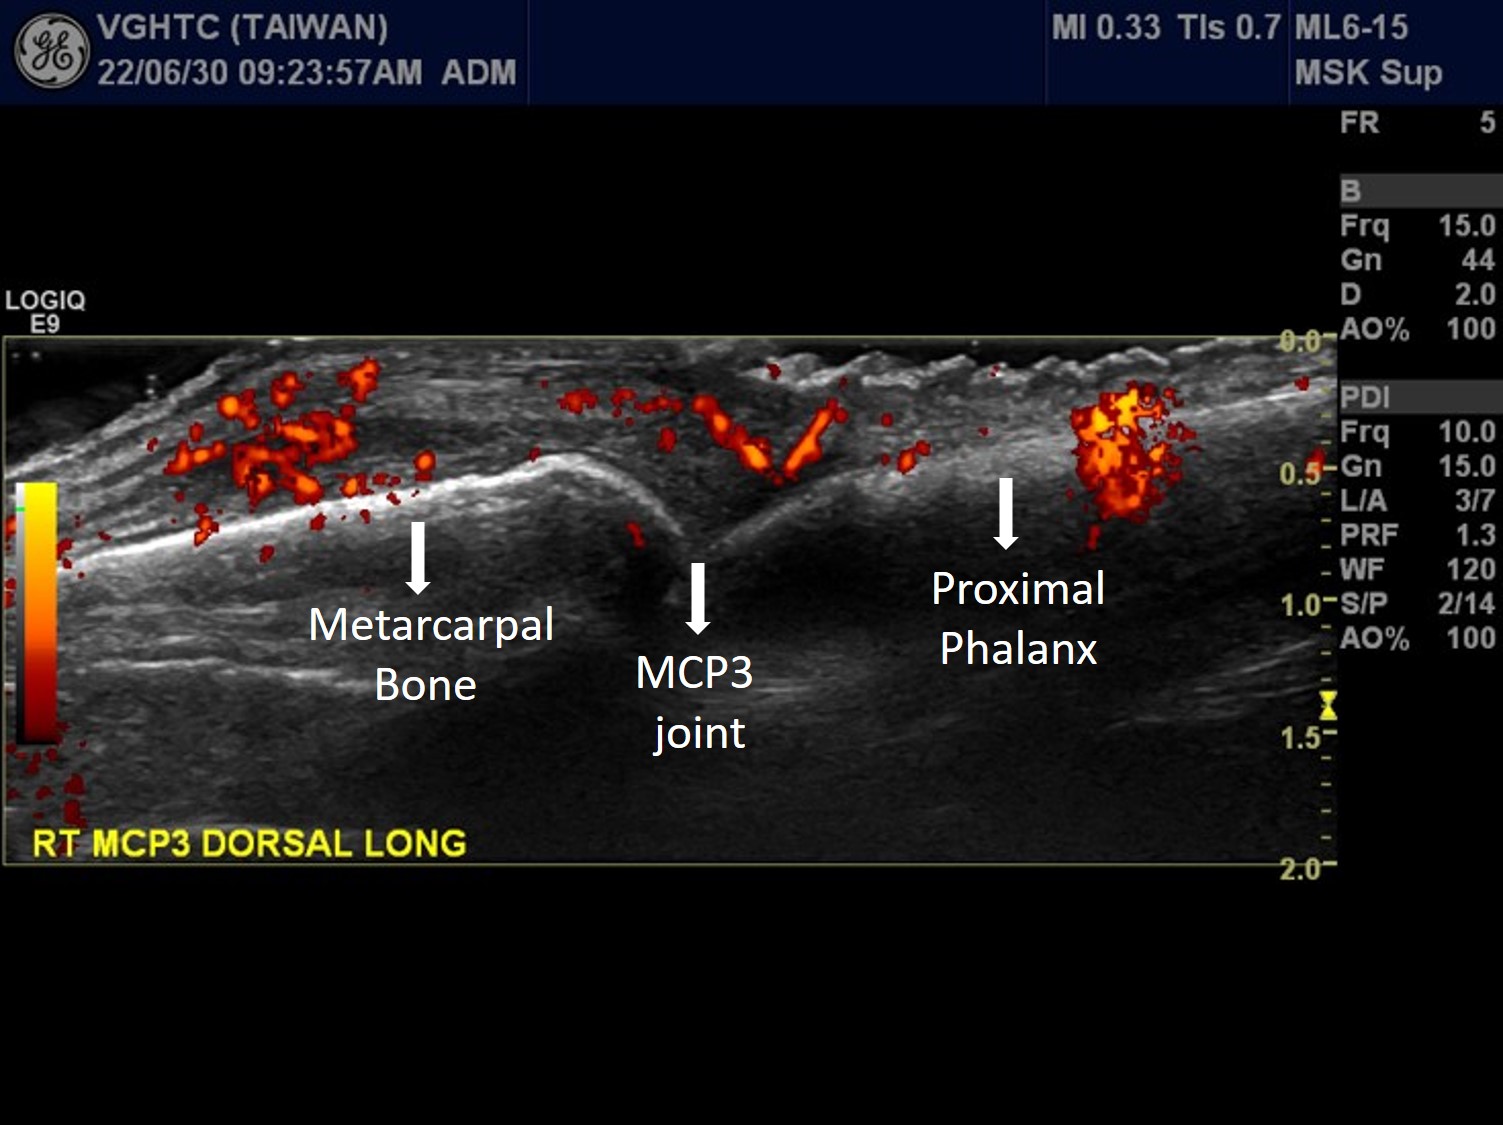

Longitudinal scan at suprapetellar region of right knee with power Doppler ultrasound showed increased joint effusion (asterisks in Picuture 6 ). Posterior longitudinal scan of right elbow with power Doppler ultrasound showed increased joint effusion at olecranon fossa (asterisks in Picutre 7) with hypervascularity (red color signal), indicating active arthritis of right elbow. Dorsal longitudinal scan at left MTP1 showed synovial hypertrophy with heterogeneous echogenicity , possible crystal deposition. (Picuture 8). Dorsal longitudinal scan with power Doppler ultrasound at right MCP3 showed synovial hypertrophy with hypervascularity (red color signal in Picture 9), indicating active arthritis.

Picuture9. Rt MCP3